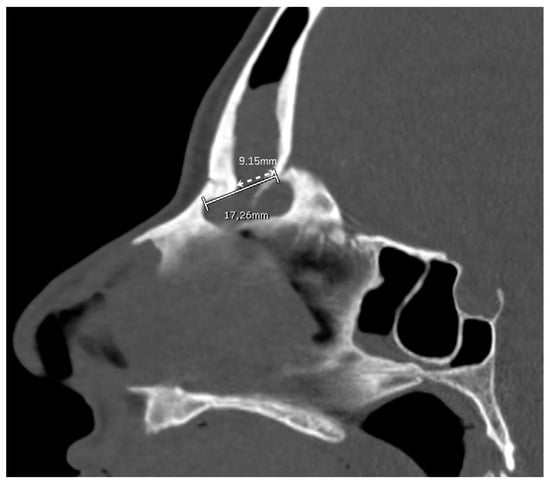

Figure 3.

A patient undergoing a DRAF III for bilateral fronto-ethmoidal rhinosinusitis. On the pre-operative sagittal CT scan, the FOAP min (dashed white line with arrows) is measured as the distance between the posterior edge of the frontal beak and the posterior wall of the frontal sinus. The solid white line corresponds to the FOAP max.